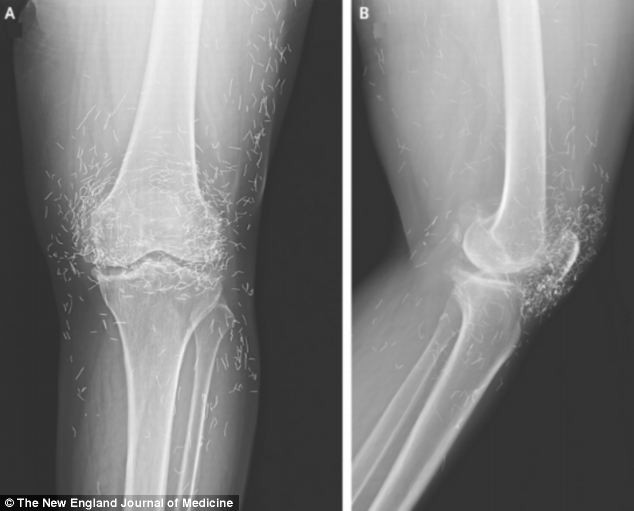

ANTĐ - Các bác sĩ đã vô cùng bất ngờ khi chụp X-Quang chân của một người phụ nữ Hàn Quốc và tìm thấy hàng trăm chiếc kim bằng vàng.

Người phụ nữ 65 tuổi này có hàng trăm chiếc kim vàng ở dưới mô đầu gối. Người ta nghĩ rằng những những chiếc kim nhỏ này đã bị sót lại khớp gối sau khi một bác sĩ trị liệu điều trị chứng đau đầu gối cho bà.

Các bác sĩ vô cùng bất ngờ trước phim chụp X-Quang đầu gối của người phụ nữ này

Ông cũng nói việc để lại những chiếc kim bằng vàng trong đầu gối có thể làm bác sĩ khó có thể hiểu được phim chụp X-Quang. Thêm vào đó, người phụ nữ này sẽ không thể chụp cộng hưởng từ, vì từ tính từ máy quét sẽ làm những chiếc kim di chuyển và làm tổn hai động mạch.